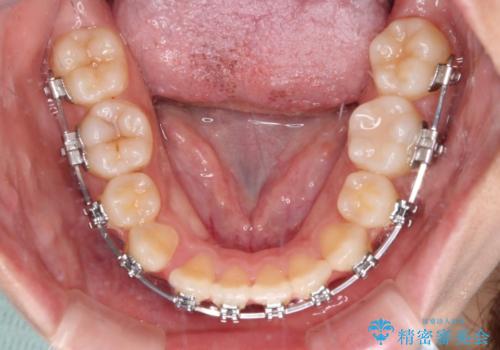

- メタルブラケット

- 1年6ヶ月

- 10-30回

舌の突出癖によるオープンバイトになっていたため、インビザラインによるマウスピース矯正をおすすめしましたが、自己管理の自信がないとのことで、ワイヤー装置による矯正治療を行うこととしました。

舌の突出癖が認められると、上下前歯の隙間を閉じることができません。

舌のトレーニングをしっかりと行っていただくことで、歯列を整えることができます。